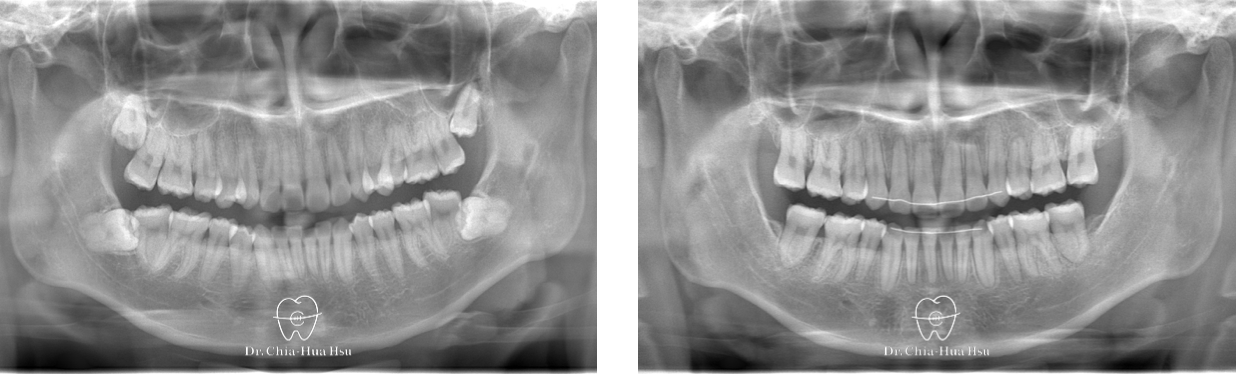

- 病患主訴:齒列擁擠、嘴微凸、中線偏移。

- 問題分析:患者嘴唇微凸、齒列擁擠、錯咬,而且中線偏移。

- 治療方式:拔除四顆小臼齒以獲取足夠空間,並使用傳統金屬矯正器搭配骨釘來退後上顎齒列並排齊牙齒。

- 治療時間:2 年 3 個月。

- 治療結果:改善齒列擁擠的問題,外觀也更好看,變成大帥哥!

治療前

治療後